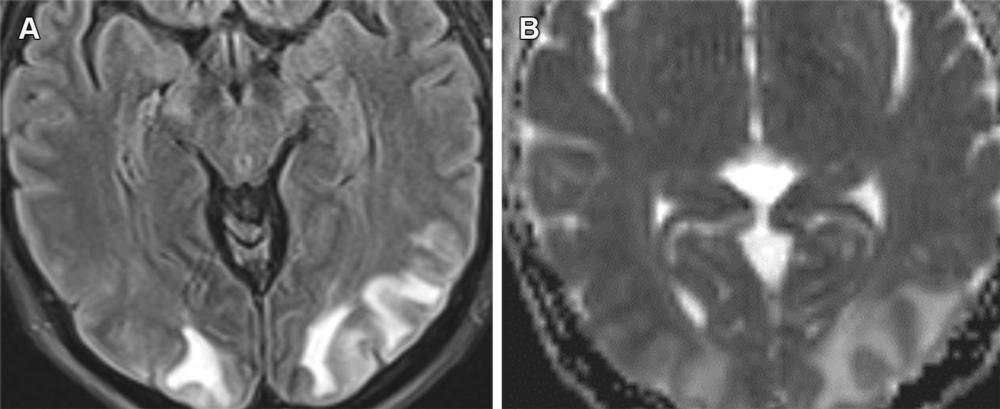

Figure 15. PRES secondary to hypertensive urgency with subcortical area of edema in the occipital lobes with FLAIR hyperintensity (A) and increased ADC values (B). ARIA-E (edema) resembles PRES, with both having a predilection for the occipital lobes with the possibility of petechial hemorrhages. However, these conditions are distinguishable based on the clinical history, with PRES usually having an acute clinical presentation.

High-res (TIF) version